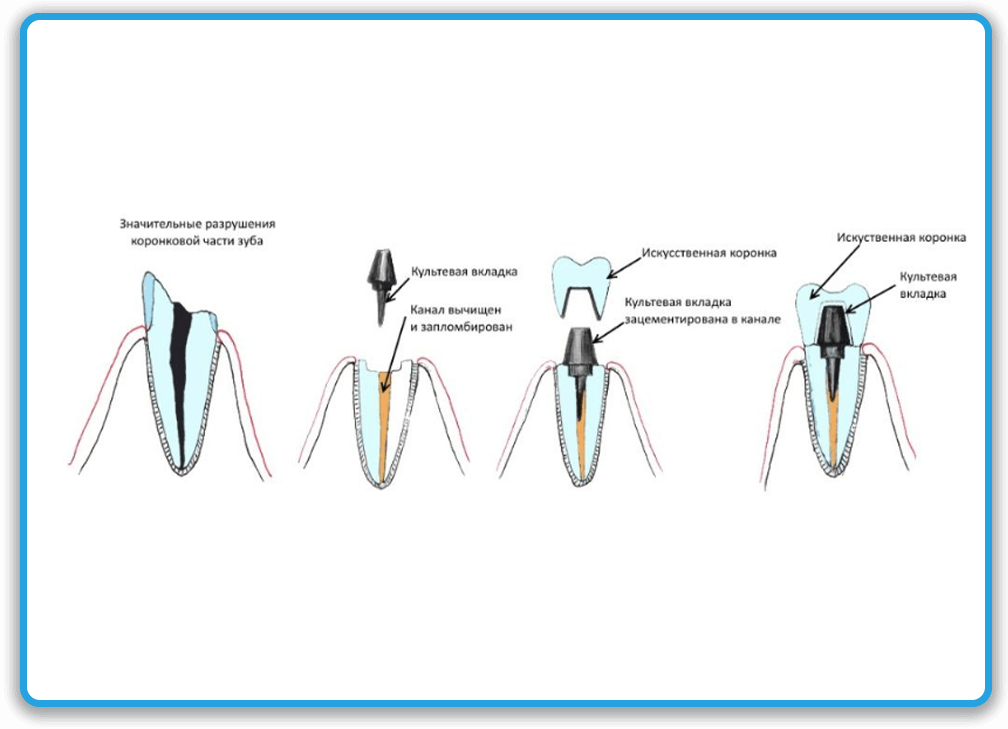

Культя зуба это

Культя зуба это 106 фото